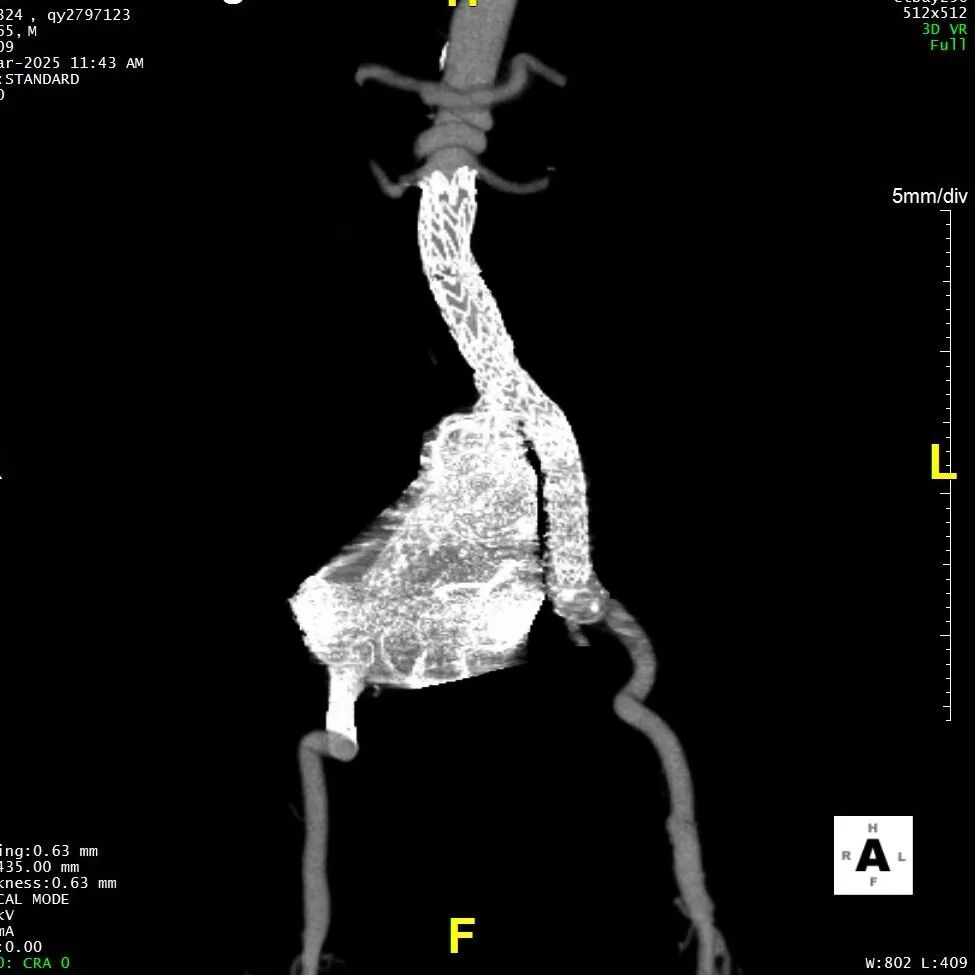

现病史:患者7小时前无明显诱因出现腹部胀痛不适,以下腹部为主,无发热、恶心、呕吐,无头晕、头痛等特殊不适,因症状持续不缓解,遂来我院急诊就诊,行腹主动脉(下腹部、盆腔段)CTA示:腹主动脉下段,右侧髂总动脉动脉瘤形成,右侧巨大髂总动脉(直径85.0mm*77.1mm)有明显造影剂溢出提示破裂,腹主动脉周围、左侧肾周、左侧腰大肌前缘及骶前积血较前明显增多,于急诊抢救室出现一过性意识丧失、血压下降休克状态,予积极补液后症状好转,现为进一步治疗,急诊以“腹主动夹层动脉瘤;髂动脉巨大动脉瘤破裂”收入院。

术前诊断:腹主动脉夹层,髂动脉瘤破裂,失血性休克。

二、术前CTA详解